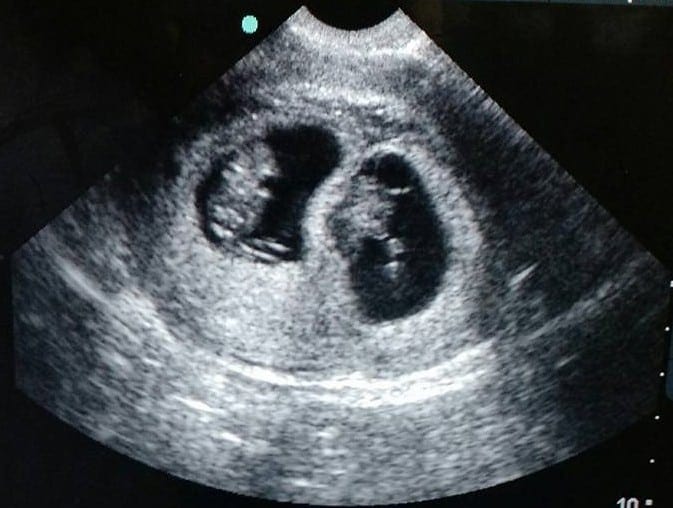

REMINDER: Don’t forget to take a belly shot! 8 week sonogram

Ultrasound Photos – 8 Week Sonogram

8 week sonogra